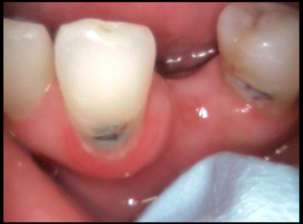

Intraoral Photograhs

Class II